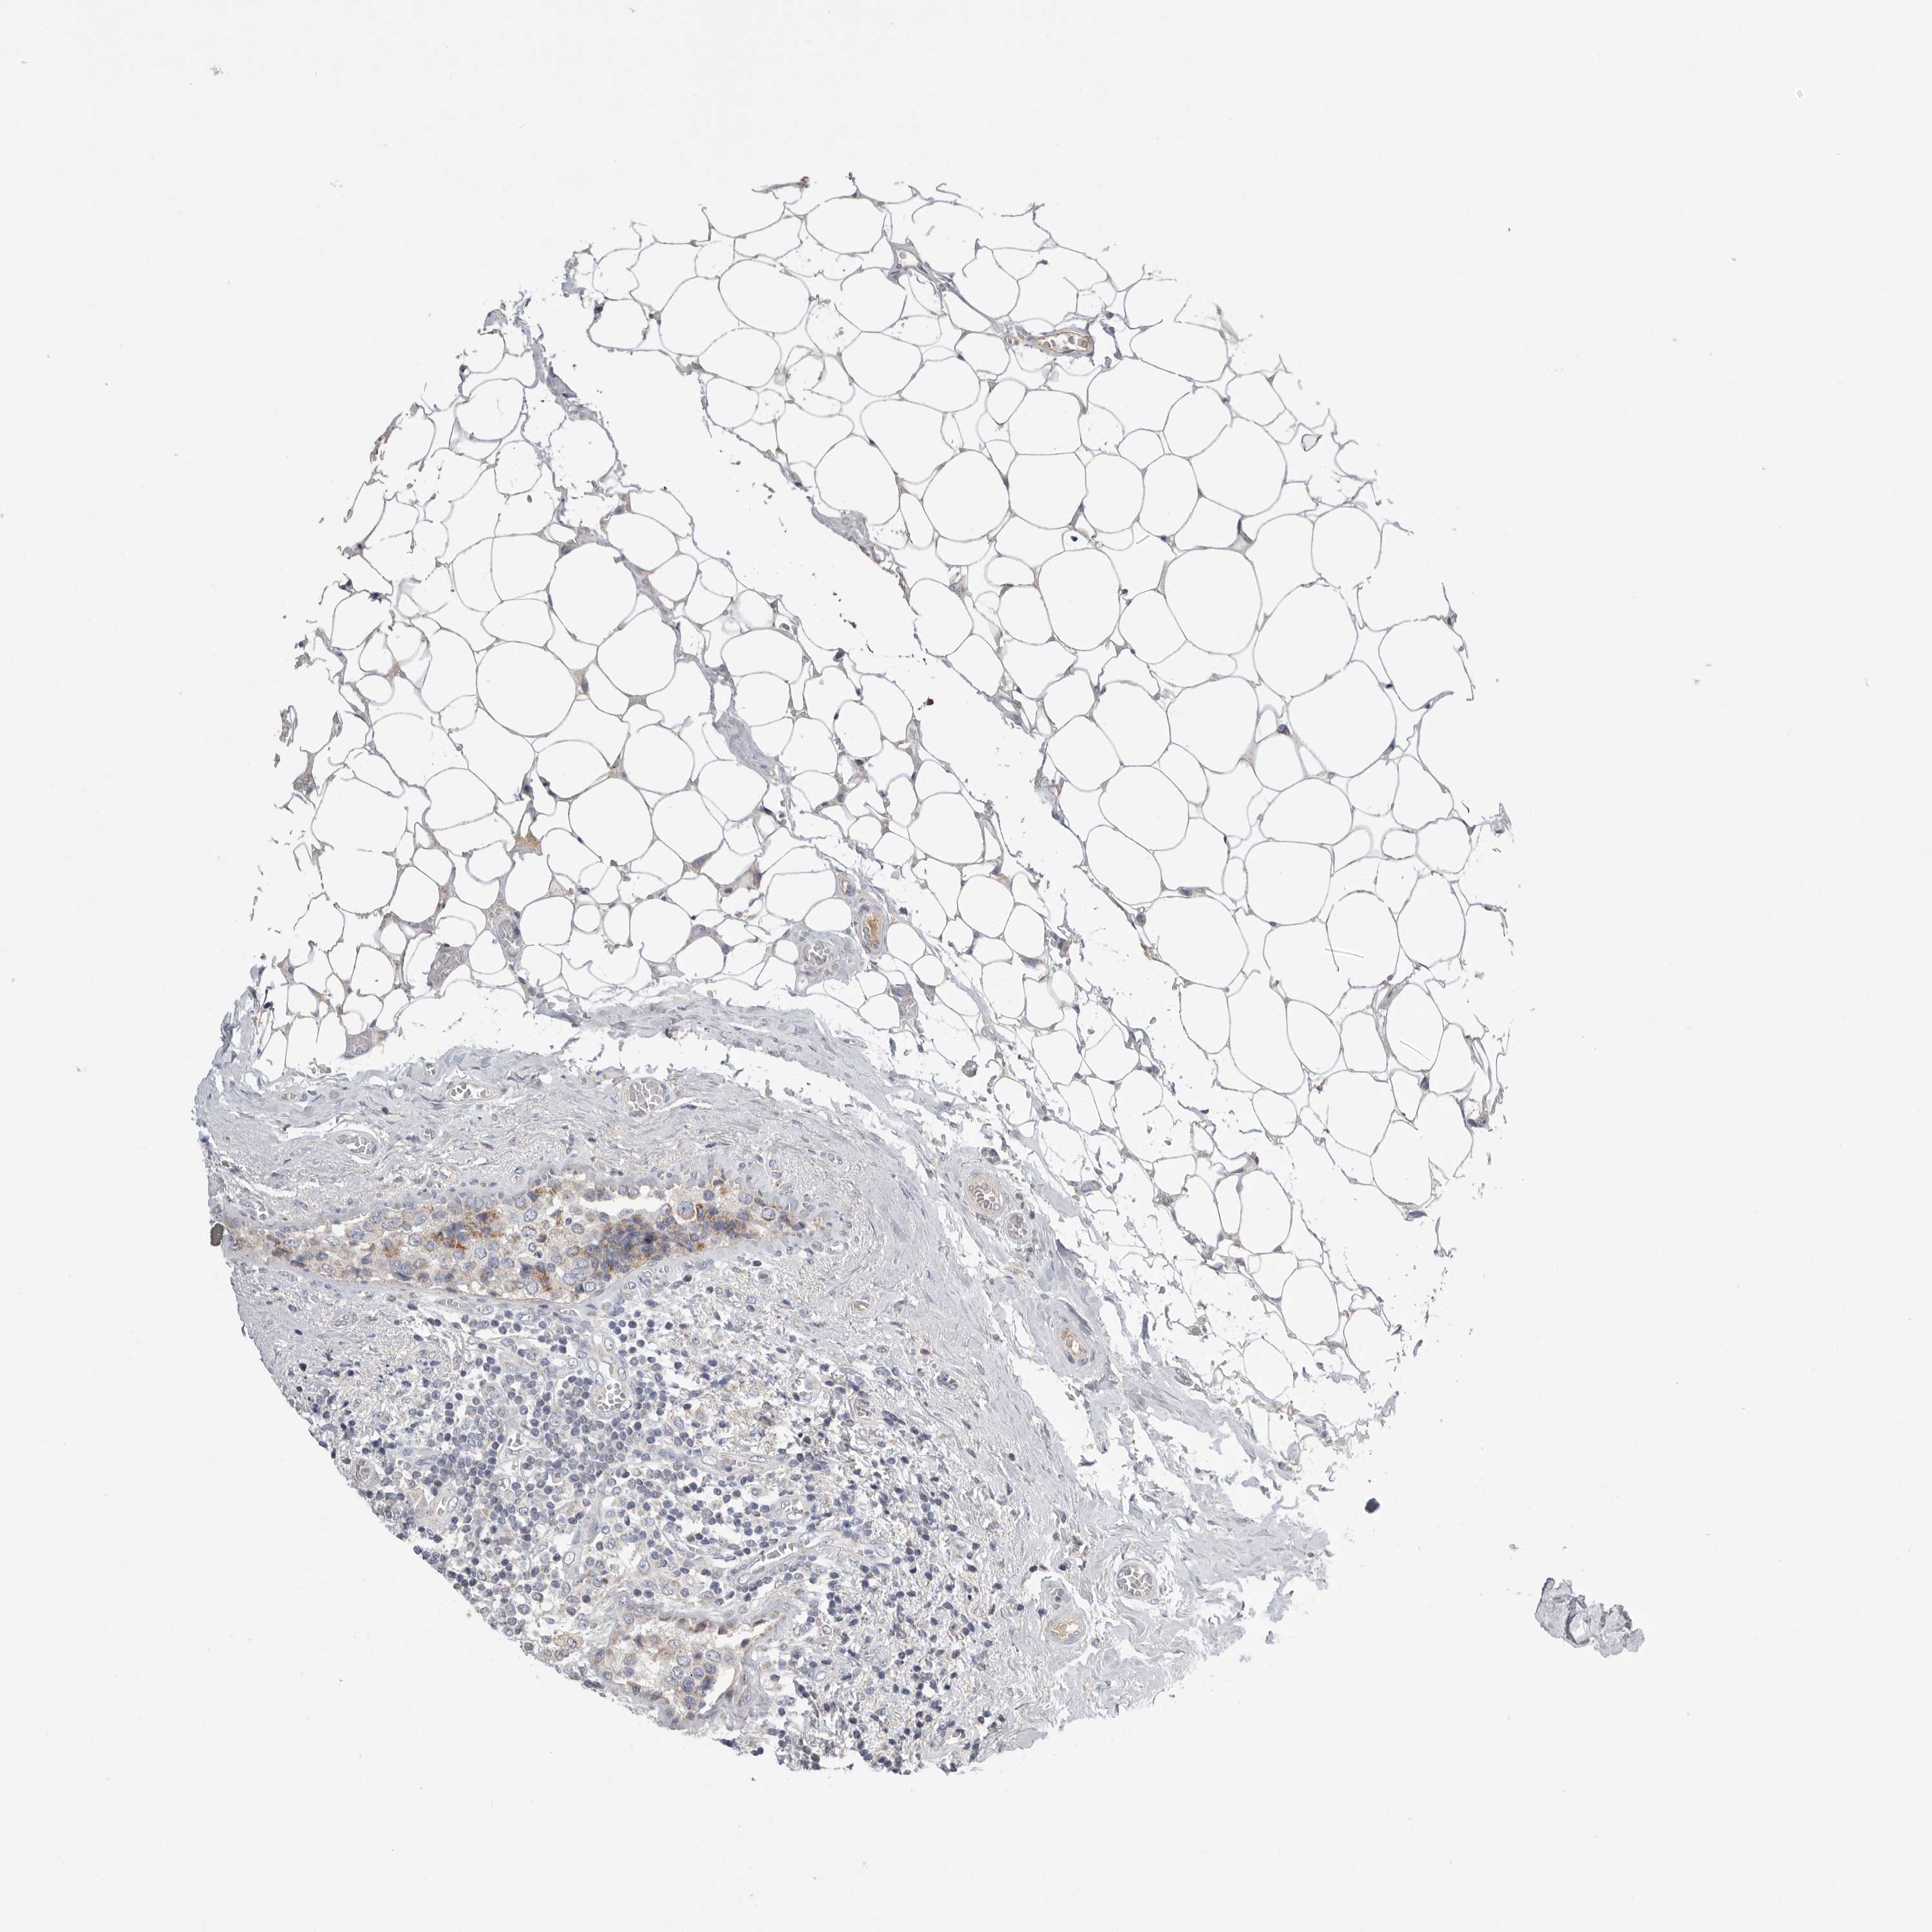

CANCER BREAST CANCER Show tissue menu

BRCA TCGA BRCA VALIDATION PROTEIN EXPRESSION

ANTIBODIES

AND

VALIDATION